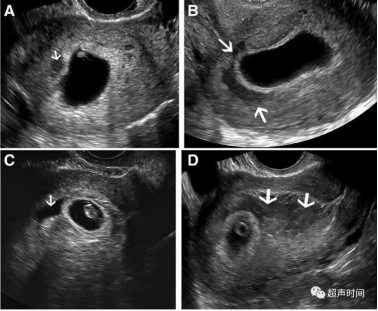

出血量不同,血肿大小形态不同;出血天数不同,血肿表现的回声强度也不同:①血肿急性期(0~48 h):血肿回声高于孕囊或绒毛膜壁。②血肿亚急性期(3~7 d):血肿回声近似于妊娠囊壁或叶状绒毛膜,血肿内回声表现趋复杂,如纤维条带样、团块状等。③血肿慢性期(>7 d):血肿呈低或无回声。

图2 箭头所指血肿大小、形态及回声均不同